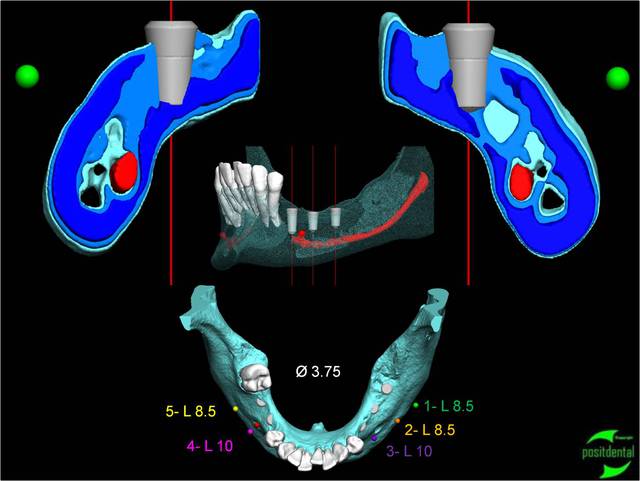

2010.04.positdental - Eugenol